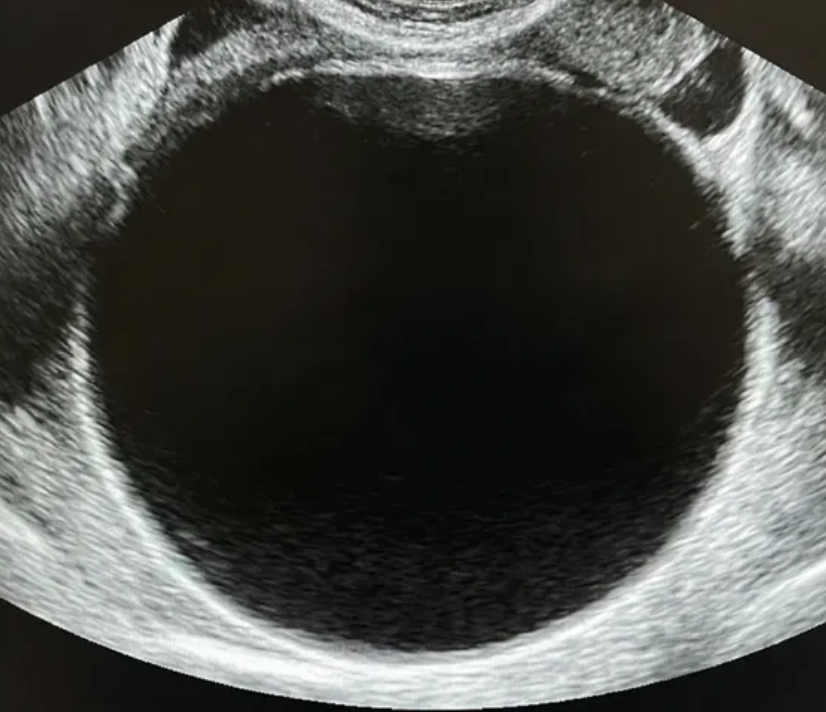

Risco: <1%Cistos simples, uniloculares lisos, lesões benignas clássicas (hemorrágico, dermoide, endometrioma, paraovariano, peritoneal, hidrossalpinge).

Achados ultrassonográficos (pré-menopausa)

Lesão benigna clássica